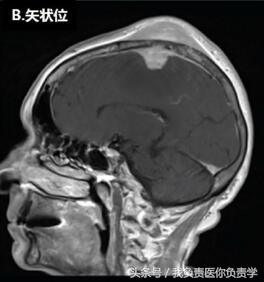

脑MRI显示,患者左侧额-顶部有一较大占位,增强扫描可见强化,从颅内、外延伸至上矢状窦(如图下所示),累及左侧额叶、顶叶和颞骨,左侧硬脑膜增厚。在颅内肿块压迫下,临近部位脑组织表现出血管性水肿。

▲头皮下占位病变。上图可见一较大的颅内外占位性病变,延伸至上矢状窦、大脑、软组织和颅骨。图(A)和图(B)T1增强见左侧硬脑膜增厚;图(C)T1可见脑水肿,图(D)为T2。